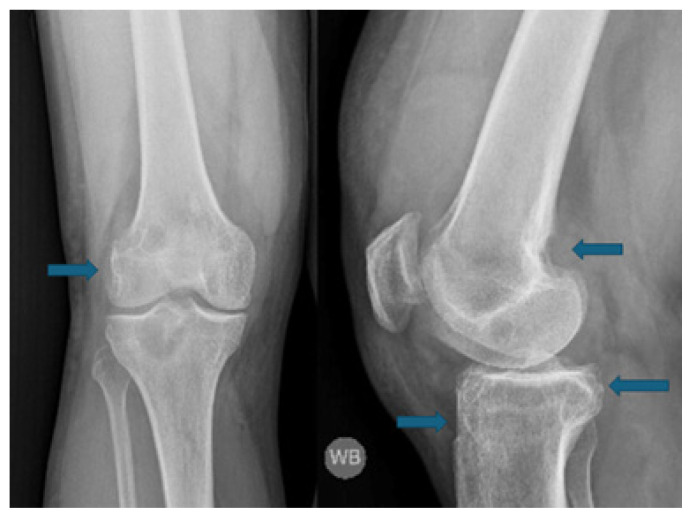

Pigmented Villonodular Synovitis: A Critical Review.